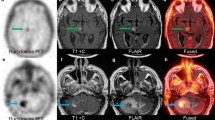

18F-Fluorocholine PET/CT images together with tumor time-activity curves and surgical samples are shown for two representative patients with (Fig. 4) and without (Fig. 5) pathologic confirmation of tumor recurrence, illustrating different 18F-Fluorocholine pharmacokinetics between lesions.

18F-Fluorocholine PET for a lung cancer patient with pathological confirmation of recurrent tumor. (A) Axial view of the last dynamic PET frame (10-min acquisition time, 30–40-min post-injection), fused with corresponding CT, showing the 11-cm3 metastatic lung adenocarcinoma in superior-anterior left frontal resection cavity with PET-derived SUVmax of 10.1. Post-Gadolinium contrast T1-weighted MRI and 18F-FDG PET are included for comparison. Color bar scales are in units of SUVbw. (B) Photomicrograph on the left panel shows metastatic carcinoma with focus of necrosis at upper right. Hematoxylin-eosin, 40x magnification. Right panel shows Ki-67 staining with a proliferative index of 90%. In total, 12 surgical samples were analyzed for this patient. All of them indicated recurrent tumor and the presence of necrosis. Highest SUVmax was 13.1. (C) Time-activity curve for intratumor area of highest 18F-Fluorocholine uptake (red). SUV, vB, K1, k2, k3, and KiP were 8.8, 0.04, 1.27 mL/min/g, 0.18 min−1, 0.17 min−1, and 0.81 mL/min/g, respectively. Corresponding values for normal brain tissue were 0.2, 0.06, 0.02 mL/min/g, 0.13 min−1, 0.13 min−1, and 0.01 mL/min/g, respectively (TAC showed in blue). Unmetabolized and metabolized 18F-Fluorocholine in plasma are shown as solid and dashed gray lines, respectively. (D) Insert from panel (C), highlighting the normal brain uptake and 18F-Fluorocholine activity in plasma

18F-Fluorocholine PET for a lung cancer patient with no recurrent tumor seen in the surgical samples. (A) Axial view of the last dynamic PET frame (10-min acquisition time, 30–40-min post-injection), fused with corresponding CT, showing the 1.4 cm3 lesion in paramedian right parietal lobe that was suspicious for viable tumor. PET-derived SUVmax was 1.7. Post-Gadolinium contrast T1-weighted MRI and 18F-FDG PET are shown for comparison. (B) The left half of the photomicrograph exhibits necrotic neuroparenchyma with fibrinous exudates. Seen in the right half are a few reactive lymphocytes and siderophages. Hematoxylin-eosin, 40x magnification. In total, 12 samples were analyzed for this patient. None of them indicated recurrent tumor, whereas necrosis was detectable in 7 out of 12 tissue samples. No evidence of proliferation was noted. Highest SUVmax derived from samples was 4.0. (C) Time-activity curve for intratumor area of highest 18F-Fluorocholine uptake (red). SUV, vB, K1, k2, k3, and KiP were 1.7, 0.06, 0.23 mL/min/g, 0.11 min−1, 0.14 min−1, and 0.13 mL/min/g, respectively. Corresponding values for normal brain tissue were 0.1, 0.07, 0.02 mL/min/g, 0.23 min−1, 0.17 min−1, and 0.01 mL/min/g, respectively (TAC shown in blue). Unmetabolized and metabolized 18F-Fluorocholine in plasma are shown as solid and dashed gray lines, respectively. (D) Insert from panel (C), highlighting the normal brain uptake and 18F-Fluorocholine activity in plasma